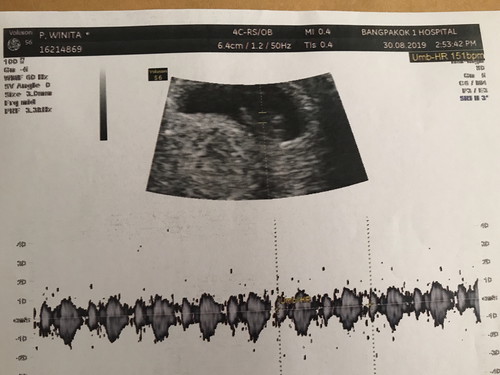

ลูกของเราตัวเล็กไปไหมค่ะ????

เป็นคุณแม่มือใหม่ค่ะ คุณหมอบอกท้องได้7วีค อยากจะทราบถึงไซต์ของเจ้าตัวน้อยว่าเท่าไรควรจะดีค่ะ?คุณแม่ตอนนี้แอบกังวลนิดหน่อยค่ะทานอะไรก็คิดเล็กคิดน้อยเปิดดูกูเกิ้ลตลอดเลยค่ะว่าอันนี้ทานได้ไหมอันนี้ดีริป่าวค่ะ คุณแม่ท่านใดพอจะแนะนำได้บ้างค่ะ ??????